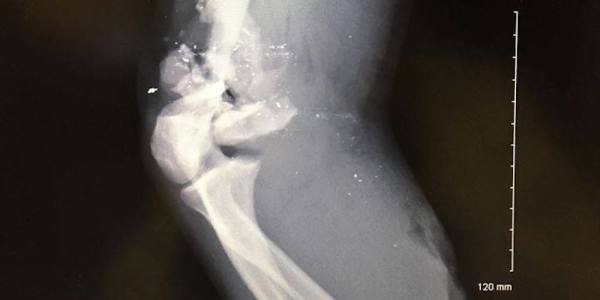

A member of the Society for Military History passes along this x-ray. It shows where a .58 caliber Minie ball hit a guy just above the elbow.

A x-ray of the elbow of a Civil War reenactor with a .58 caliber Minie ball embedded withinDavid Welch/Society of Military History

David Welch, the member of the society, comments: “ I thought people might appreciate this rare glimpse into the damage that Civil War weapons could bring on the soldiers’ bodies. As you can see from the images, if it were not for modern medicine and many titanium screws and plates, he would have lost his arm — amputation that would have been necessary above the elbow.”